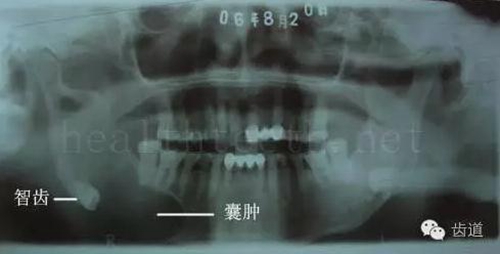

九、關(guān)于智齒(第八顆牙)

智齒造成的頜骨囊腫,手術(shù)切除后需要植骨